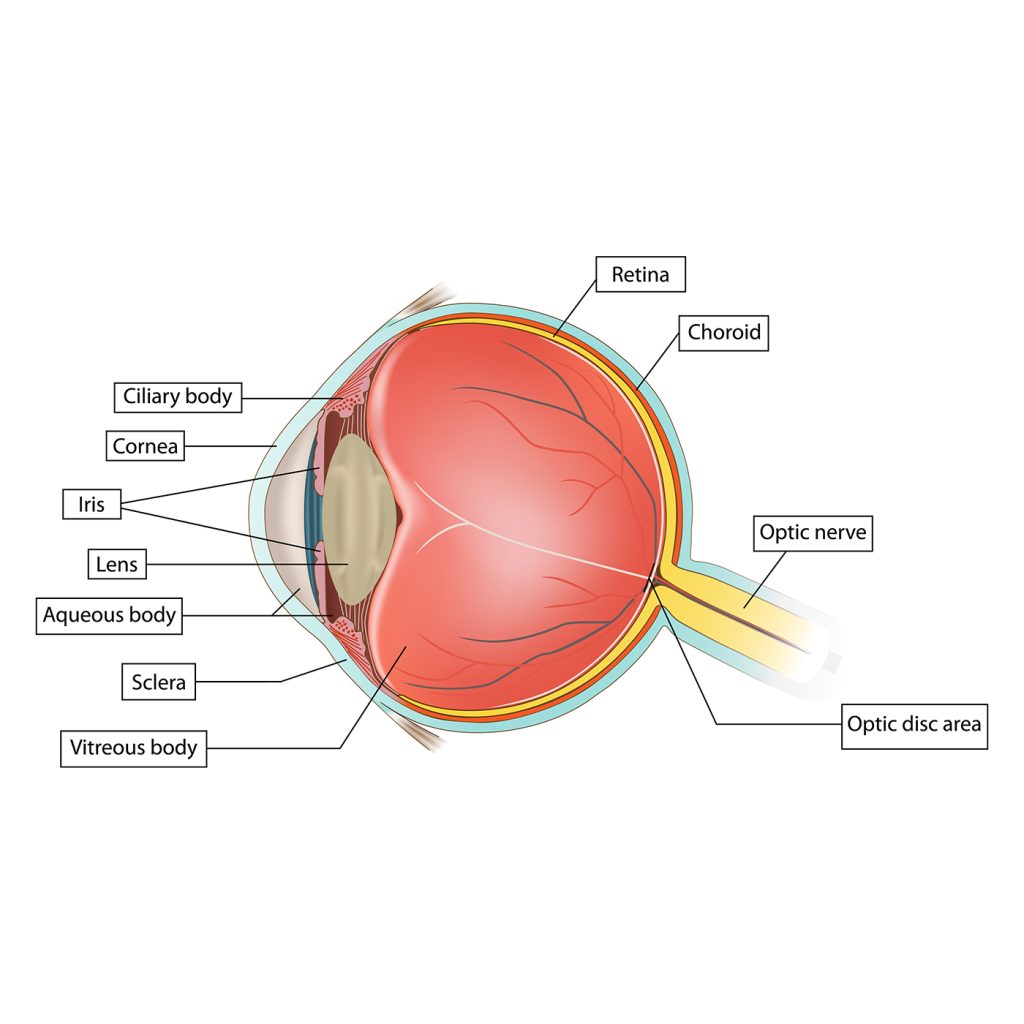

Mijn kat is ineens blind, hoe kan dit?